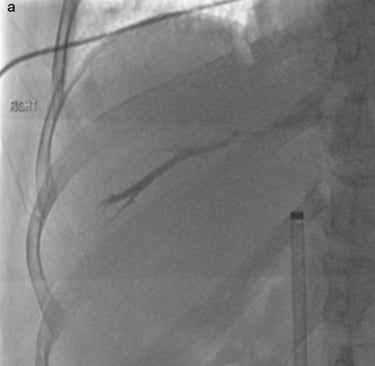

Punción y colocación de guía transhepática hacia la unión cavoatrial inferior

Implante de cateter transhepático